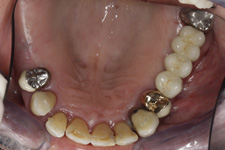

Během let může postupnou ztrátou zubů zůstat v ústech omezený počet zubů, které umožňují držení zubních náhrad.

V důsledku přetížení zbylých zubů např. houpavými pohyb snímacích náhrad dochází k uvolnění těchto zubů a držení můstků a protéz je tak velmi těžké. V těchto případech můžeme pomocí implantátů zvýšit počet pilířů a tím zabránit přetěžování a ztrátě zbylých zubů